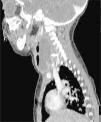

Se han recuperado estudios de imagen de 63 pacientes, a los que se les realizaron 71 pruebas. Las técnicas utilizadas han sido 36 TAC (50,7%), 20 ecografías (28,2%), 8 radiografía lateral de cuello (11,3%) y 7 RMN (9,9%). Al 62,5% (5 de los 8) de los que se realizó radiografía lateral de cuello y al 15% (3 de los 20) de los pacientes a los que se les realizó ecografía, hubo que completarles el estudio con TAC o RMN. A los pacientes a los que se les realizó TAC o RMN no hubo que hacerles más pruebas de imagen. La TAC ha sido empleada fundamentalmente en ACPI de localización más profunda (ARF, APA y APF), mientras que la ecografía fue empleada en ACPI más superficiales (AA y AS) (figs. 1 y 2).

Las técnicas de imagen más utilizadas han sido la TAC y la ecografía, empleadas en un 86% de los casos. Se usó cada una en diferente situación: la TAC preferentemente en abscesos de localización profunda y la ecografía en abscesos superficiales. La TAC se ha usado en el 100% de los APF y en el 75% de los ARF. La ecografía se usó en el 78% de los AS y en el 70% de las AA, siendo, no obstante, la prueba inicial en muchos casos con objeto de evitar radiaciones innecesarias a niños de corta edad14. Aunque la TAC supone una prueba que requiere colaboración del paciente (puede precisar sedación) e implica radiación del niño, en nuestra opinión es la prueba de elección ante ACPI de localización profunda, si hay mala respuesta al tratamiento o ante la sospecha de complicaciones y es, además, la herramienta más útil para la planificación de la cirugía3–5. La radiografía lateral de cuello, bastante utilizada en los servicios de urgencias, se ha usado solo en 8 ocasiones, todas en ARF, y en nuestro caso con una clara tendencia a la disminución en su uso. Por otro lado, en los últimos años estamos empleando más la RMN tanto como herramienta diagnóstica como para control radiológico ante la sospecha de persistencia de un ACPI tras la cirugía, evitando así radiaciones a los niños.